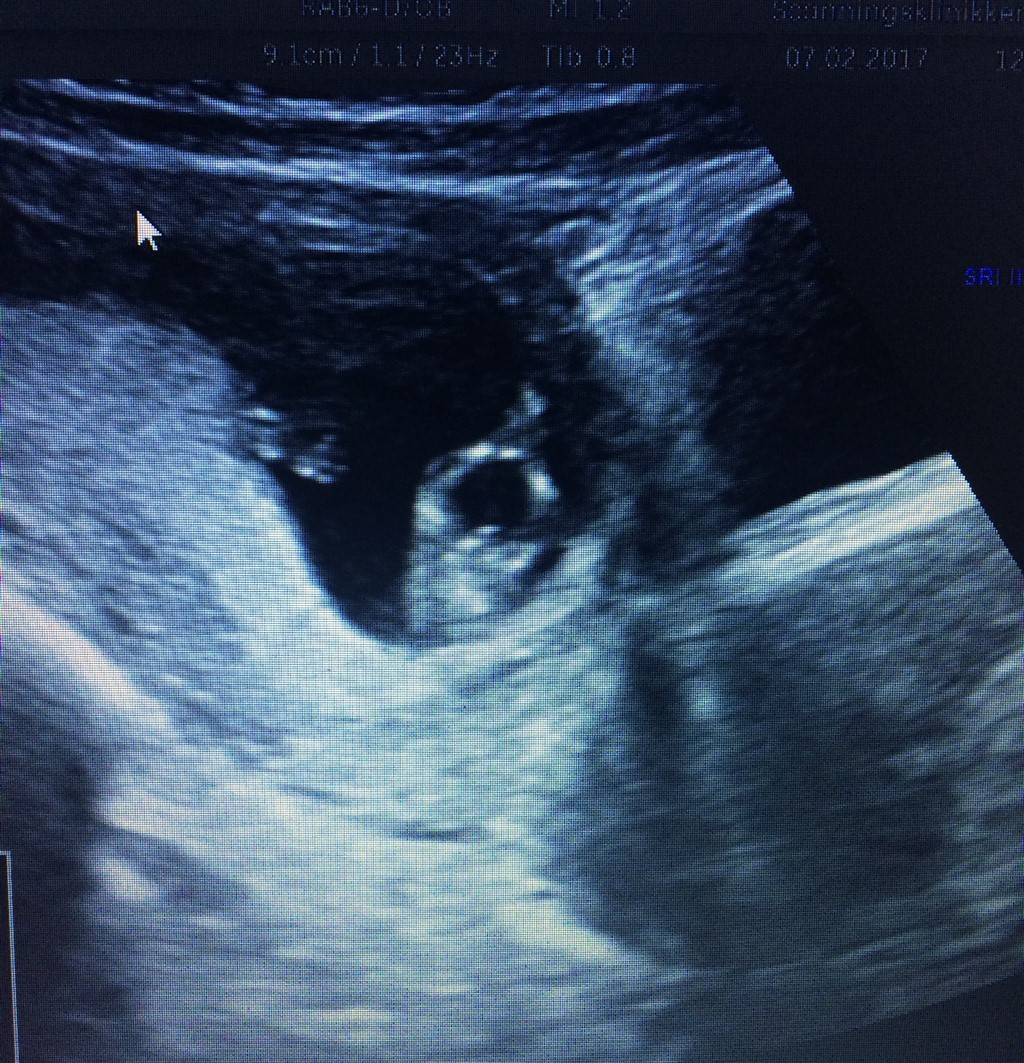

Er i uge 11 på scanningen. Og ved der sidder mange eksperter herinde aner ikke hvad man skal kigge efter  tør i give et bud?? På et af billeder bagfra kan man tydeligt se en tap. Men hun sagde det både kunne være tissemand og klit

Relativt flad pande og burgerlinjer i ryggen på billede 3, umiddelbart en pige

Linjerne langs med ryggen der får maven og ryggen til at ligne en burger